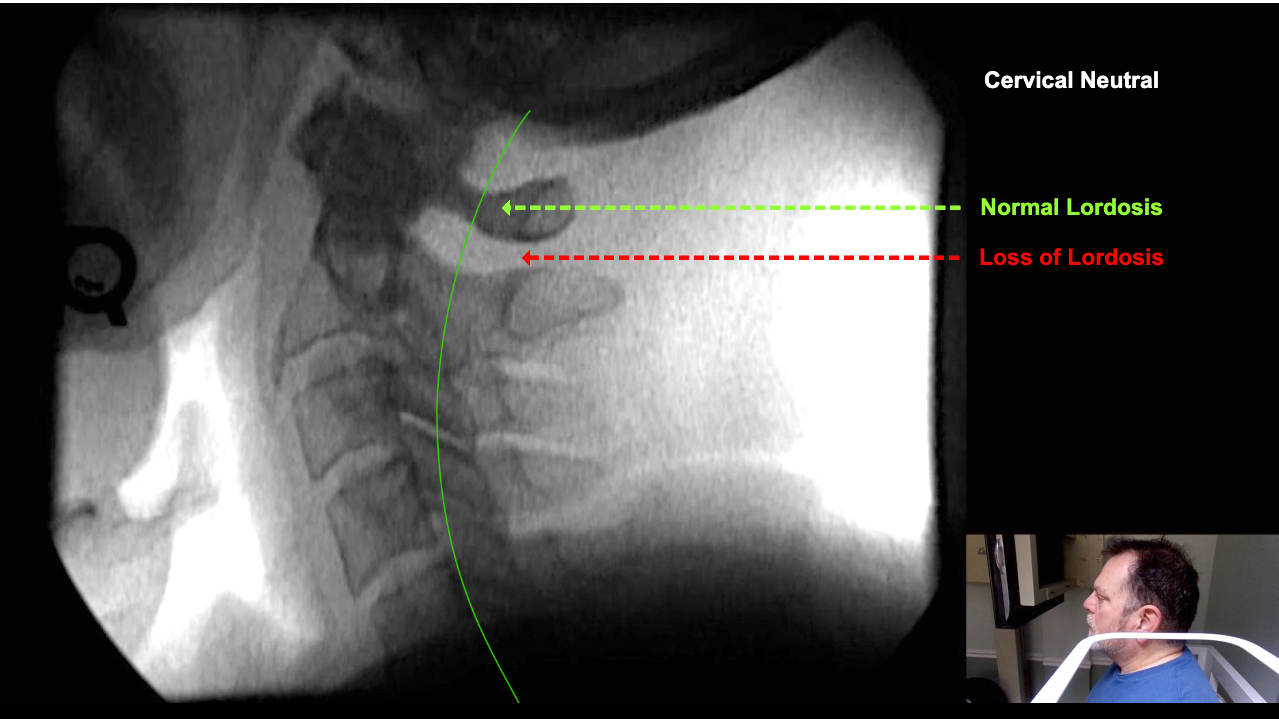

Image 2